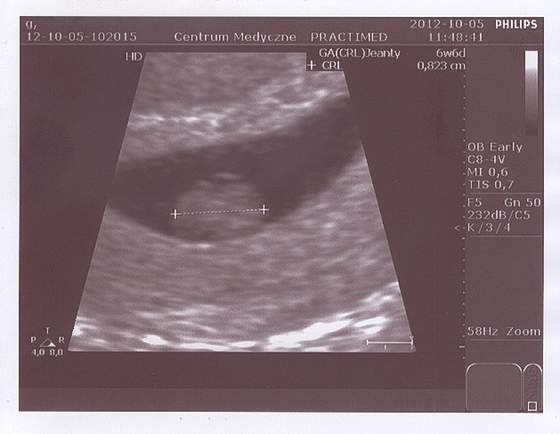

a tu zdjecie :) hehe.jpg

jestem... widziałam serduszko... lekarz zmierzył i powiedział ze wielkością na 6t5d...